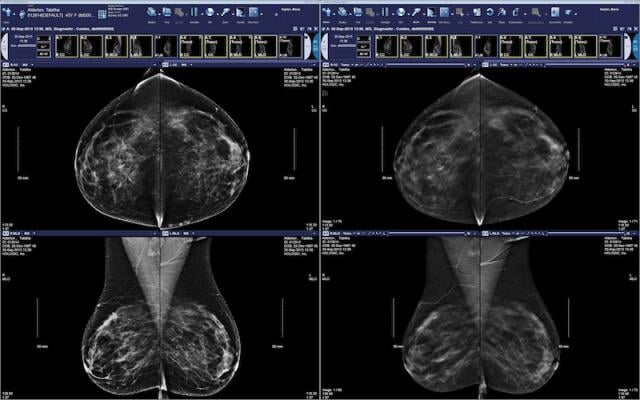

McKesson Radiology Mammography Plus introduces innovative, user-inspired workflows for digital breast tomosynthesis, breast density and BI-RADS (Breast Imaging-Reporting and Data System) assessment while leveraging the high performance of McKesson Radiology PACS with 64-bit technology to offer advanced breast imaging workflow with the proven efficiency and individual customization inherent in McKesson PACS.